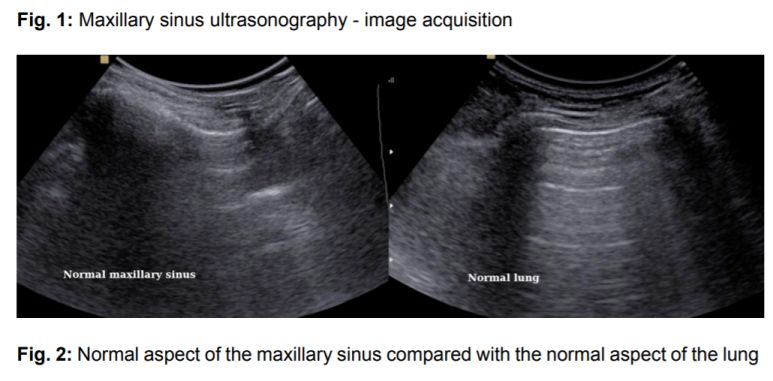

좌측: 정상 부비동 / 우측: 정상 폐

Ref.> Maxillary sinuses ultrasonography - a reliable method in the diagnosis of acute sinusitis in children, ECR 2012

정상 부비동은

폐(Lung)처럼

공기로 가득 차있어서

Air Artifact만 나타납니다.

공기의 공명으로 인해

초음파 빔이 투과하지 못하고

흩어져버립니다.

때문에

부비동 벽의 경계가

보이지 않습니다.